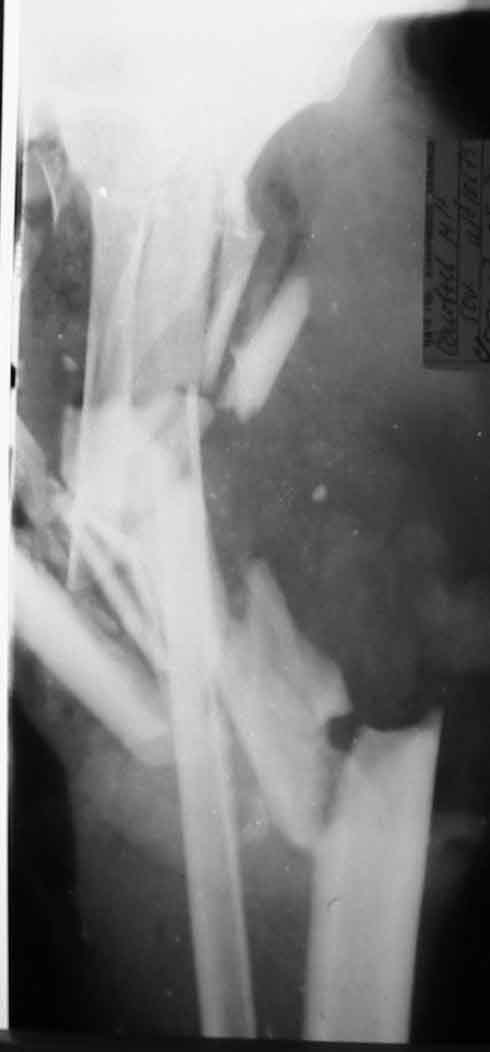

Больной С., 50 лет, строитель, поступил в 64 ГКБ 17.05.02., доставлен СП.Травма за 1 час до поступления на работе на ноги пострадавшего наехал трактор. При поступлении больного тяжелое, сознание спутаное, больной возбужден, не критичен. Кровотечения нет. Кожные покровы бледные. Пульсация на периферических артериях слабо определяется. АД 80/60 мм рт ст. Справа закрытый перелом большельшеберцовой без смещения.На Р-граммах левой голени многооскольчавый перелом костей с/3 в/3 голени (см 1)). Другие сегменты не пострадали.ДЗ. Открытый Многооскольчатый раздробленный перелом костей левой голени. Разможжениемягких тканей левой голени. Закрытый перелом с/3 большеберцовой кости правой голени со смещением. Вывих головки малоберцовой кости. Травматический шок 2-3 ст. Минуя приемное отделение больной поднят в экстренную операционную. После выведения больного из шока выполнена ПХО, и учитывая разможжение мягких тканей левой голени и многооскольчатый характер перелома - ампутация левой голени на границе в/3, экзартикуляция м/берцовой. Решено было максимально сохранить длину конечности. Ранане ушивалась, наложены провизорные швы (см 2, 3).На правую голень фиксирована разрезной гипсовой повязкой.Производились перевязки Н2 О2 , повязки с левомеколем, по мере спадения отека дозировано подтягивались провизорные швы. По состоянию на 24.05.02 Состояние больного удовлетворительное, субфибрильная лихорадка.Местно: в рану выстоят опил б/берцовой кости, кожный лоскут "болеет", некроз мышц иподкожной клетчатки в наружном углу раны (см 4).Вопросы:-Оправдана ли сберегательная тактика при поступлении?-В последующем имеет ли смысл постараться сберечь максимально возможную длинусегмента? -Если да то как заместить дефект тканей?-Если нет то какой вид ампутации выбрать и на каком уровне?Глеб КоробушкинАспирант Кафедры травматологии и ортопедии РГМУ, Москва